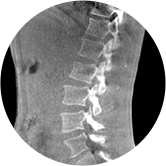

三维脊柱应用

精准诊断

手术方案规划

术后随访

• 脊柱评估

传统方法都是在二维平面,依靠棘突或椎弓根相对于椎体的偏移来评估脊柱侧凸。WR-3D可以更精准评估脊柱侧凸,制定手术方案,可以更直观地显示和量化椎体的平移和轴向旋转,术后评估更准确客观。

• 全身姿态评估

WR-3D能提供一种负重位状态下全身的姿态和三维空间任一平面平衡评估,使全脊柱术后评价更客观、真实 。通过各种临床参数包括骨盆、脊柱参数评价骨盆、脊柱平衡,避免由于髋膝屈曲造成的代偿性脊柱失衡的发生,WR-3D提供了三维空间任一平面平衡评估测量方法,可以更加定量地评估手术效果 。